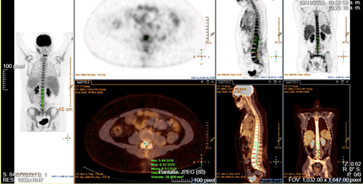

PET-TC con 18F-FDG: Hallazgos que sugieren proceso lifnoproliferativo con afectación nodal supradiafragmática e infradiafragmática por presencia de foco hipermetabólico único peripancreático, asi como afectación medular D11-S1 en contexto de neurolinfomatosis (Figura 3).

Figura 3 PET-TC con 18F-FDG con hallazgos con afectación medular D11-S1 en contexto de infiltración neoplásica axial extramedular intrarraquídea.

Durante su estancia en planta de Hematología, el paciente se mantiene clínica y hemodinámicamente estable. Se realiza nuevamente un PET-TC tras quimioterapia 1 mes después, con importante mejoría de la captación en canal medular. Asimismo, se realiza aspirado de médula ósea de control 2 meses después del primer aspirado, que confirma remisión completa morfológica con 0.6% blastos y con BCR-ABL en sangre periférica y médula ósea negativos.